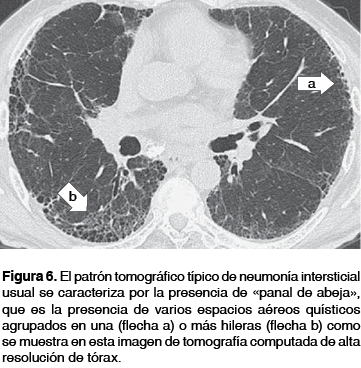

Neumonia intersticial no especifica definicion. Diagnostico Cabe señalar que en la neumonía intersticial no especifica, algunos autores mencionan que en procesos manifiestos de entidades clínicas diferentes se adjudica ser parte de esta afección por tal razón dicen que forma parte de ese conjunto de anomalías pulmonares intersticiales difusas que refieren cuadros de reportes clínicos de la sintomatología. Curable con corticoides o inmunosupresores La neumonía intersticial descamativa (NID), la bronquiolitis respiratoria asociada a enfermedad pulmonar intersticial (BREPI) y la neumonía intersticial no específica (NINE) en general tienen una evolución más lenta con mayor respuesta a la terapéutica y mejor pronóstico 12 IV lb EXÁMEN. Inconsistente com pneumonia intersticial usual, com diagnóstico de pneumonite de hipersensibilidade crônica Imagem de TCAR do tórax em janela de pulmão no plano axial evidenciando opacidades reticulares esparsas com bronquiolectasias de tração, destacandose importante acometimento do feixe peribroncovascular no lobo superior direito (seta).